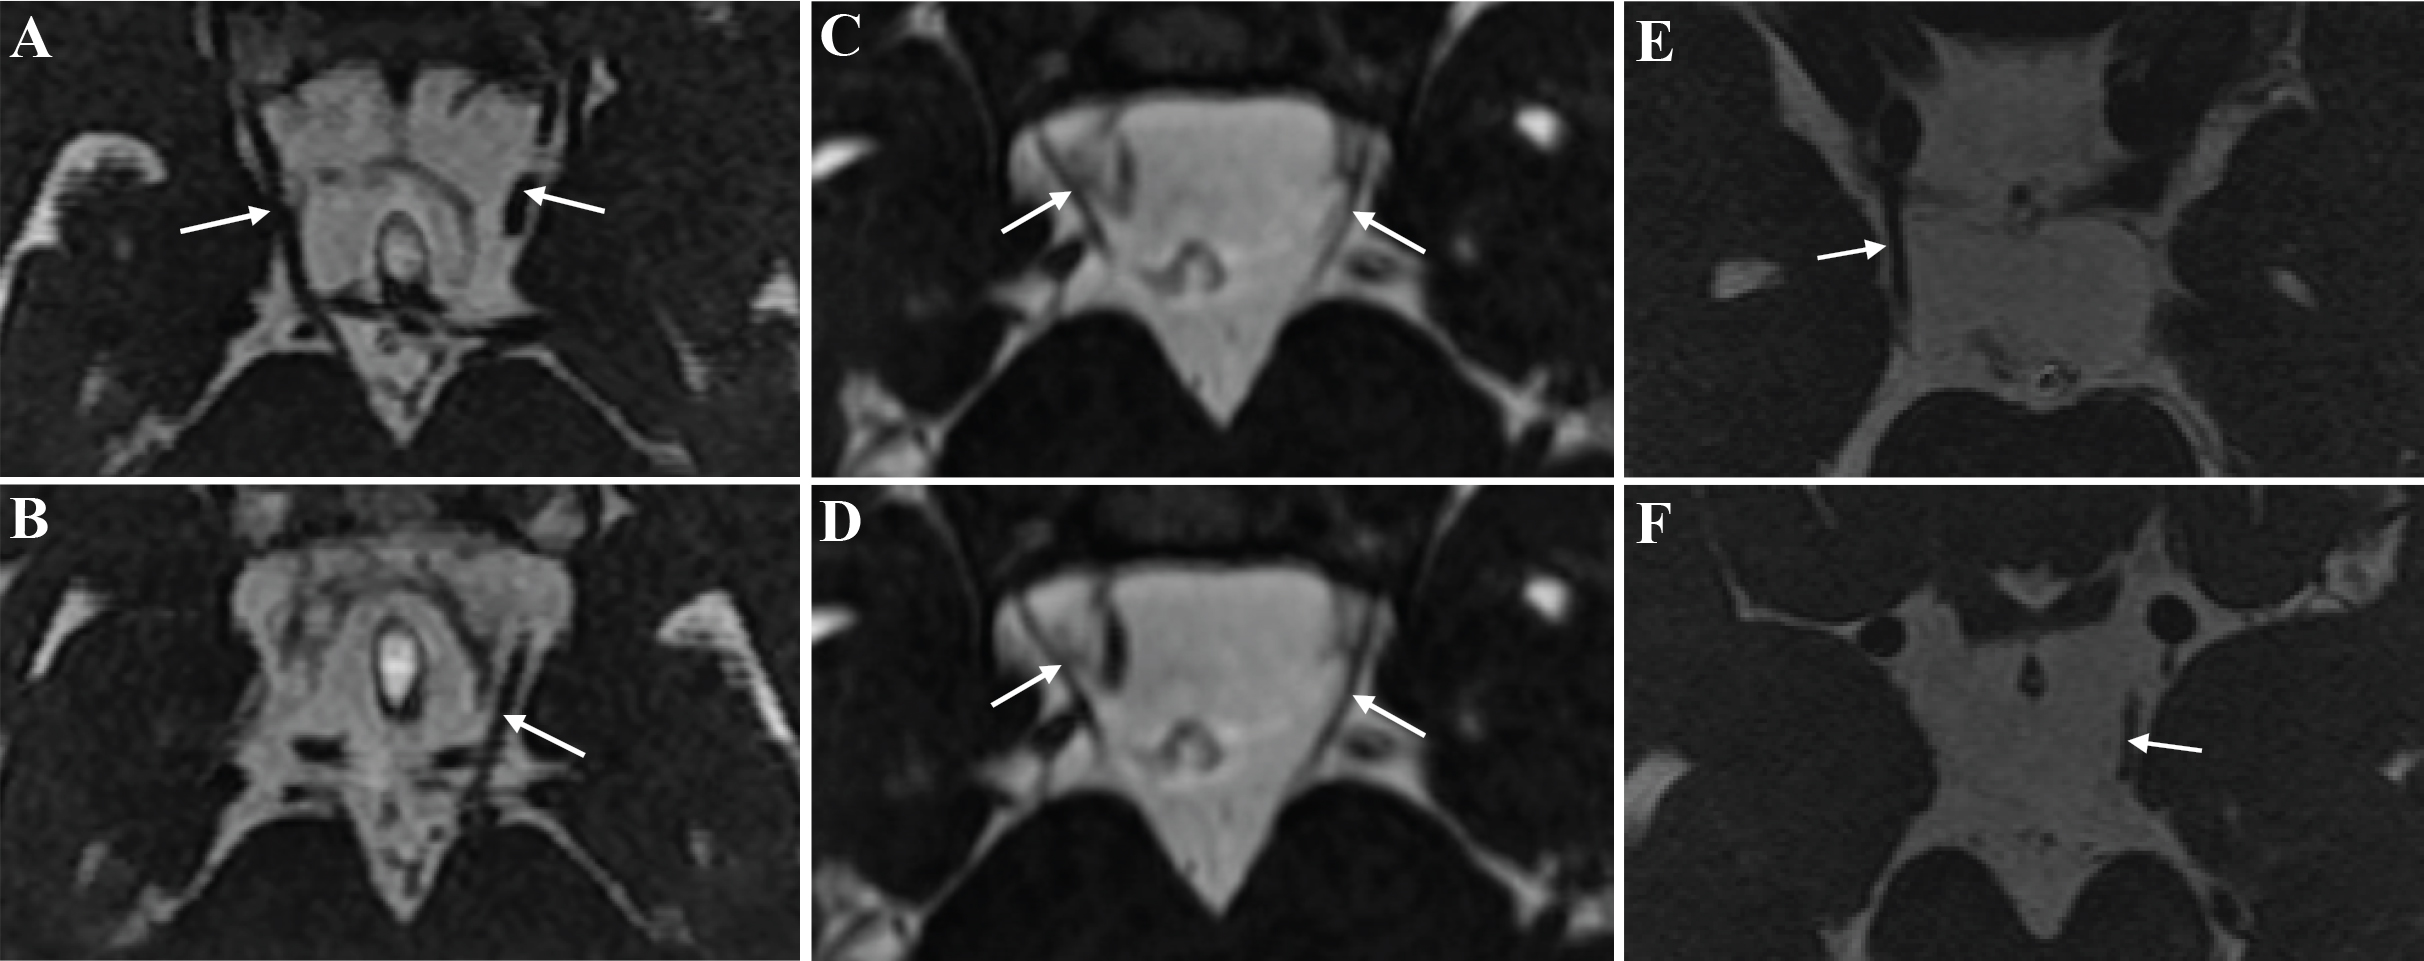

Figure 4. Imaging of the oculomotor nerves. A–B: Bilateral oculomotor nerves demonstrated by the axial magnetic resonance imaging (MRI) of a normal control. C–D: The axial MRI indicates bilateral hypoplastic oculomotor nerves in patient II:1. E–F: Patient II:2 presented hypoplasia similar to that of patient II:1, according to the axial MRI.